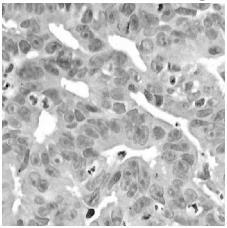

The proposed methods were applied on different digital images and some results are given below. Each figure indicates the original image, output image of three filter. By comparison of these three pre-processing techniques, progressive switching median filter provides betterresultswithlowMSE,highPSNRandSSIMvalues.

a) Original image

b) Gaussian filtered image c) Wiener filtered image

d) Median filtered image

Output images of Gaussian filter, Wiener filter, Progressive switching median filter.